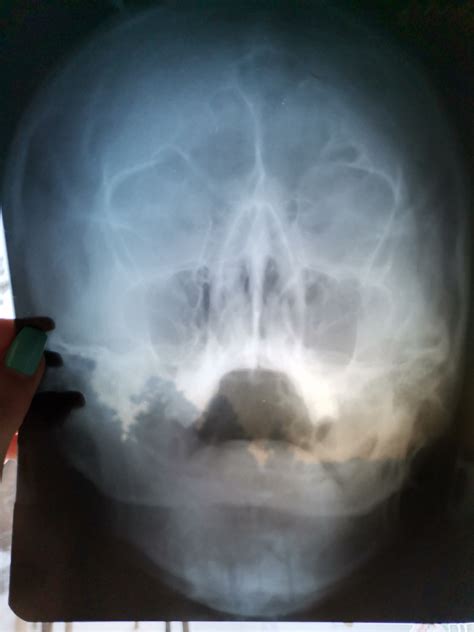

Заложенность носа + снимок - Вопрос лору - 03 О...